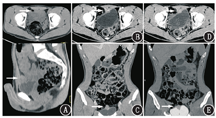

患者男,27岁,3个月前因肉眼血尿在当地医院行膀胱镜检查,于膀胱底部见2.0 cm×2.5 cm乳头状肿物,质脆,触之易出血。随后行经尿道膀胱肿瘤电切术,术后病理示膀胱浸润性腺癌,浸润至固有膜,提示临床关注病灶是原发还是转移性,有否腺癌病史,特别是大肠癌、前列腺癌病史。术后患者继续出现肉眼血尿,入住本院进一步诊治。体格检查无特殊,肿瘤标志物[癌胚抗原(carcinoembryonic antigen, CEA)、甲胎蛋白(alphafetoprotein, AFP)、铁蛋白(ferritin, FERR)、糖类抗原(carbohydrate antigen, CA)125、CA15-3、CA19-9、总前列腺特异抗原(total prostate specific antigen, tPSA)、游离前列腺特异抗原(free prostate specific antigen, fPSA)、fPSA/tPSA、鳞状细胞癌(简称鳞癌)抗原(squamous cell carcinoma antigen, SCCA)、细胞角蛋白19片段(cytokeratin 19 fragment, CYFRA21-1)、CA72-4、神经元特异性烯醇化酶(neuron-specific enolase, NSE)]、肝肾功能电解质全套及大便常规均未见异常。原病理切片会诊意见为:膀胱中等分化腺癌,结合免疫组织化学检查结果,考虑肠道来源可能性大。本院CT泌尿系统成像检查(图1)示膀胱顶前壁实性肿块,突向膀胱外生长,周围组织间隙较清晰,大小为1.2 cm×2.4 cm×3.1 cm,呈明显不均匀强化。为进一步明确病变性质、查找膀胱外可疑原发灶及其他部位转移灶,行18F-脱氧葡萄糖(fluorodeoxyglucose,FDG)PET/CT(德国Siemens mCT-s64型)全身显像。检查前患者禁食6 h、测血糖(5.6 mmol/L),静脉注射18F-FDG 229.4 MBq(患者体质量58 kg),平静休息1 h后显像。嘱患者口服呋塞米20 mg、多饮水、多排尿,以促排膀胱尿液放射性,2 h后行腹盆腔延迟显像(检查前饮水憋尿),影像表现(图2):膀胱顶前壁软组织肿块,18F-FDG摄取异常增高,早期及延迟最大标准摄取值(maximum standardized uptake value, SUVmax)分别为24.8、26.7;双侧盆壁未见明显肿大淋巴结;肠管及全身其他部位未见明显异常18F-FDG高代谢灶。PET/CT显像提示膀胱恶性肿瘤性病变,未见淋巴结及远处转移。随后的肠镜检查未发现明显异常。最终行腹腔镜下膀胱扩大切除术及双侧盆腔淋巴结清扫术,术后病理检查示:膀胱中等分化脐尿管腺癌,肿瘤从膀胱浆膜层浸润至固有层并伴坏死及多核巨细胞反应;双侧盆腔共17枚淋巴结未见癌转移;脐周皮肤未见癌浸润。